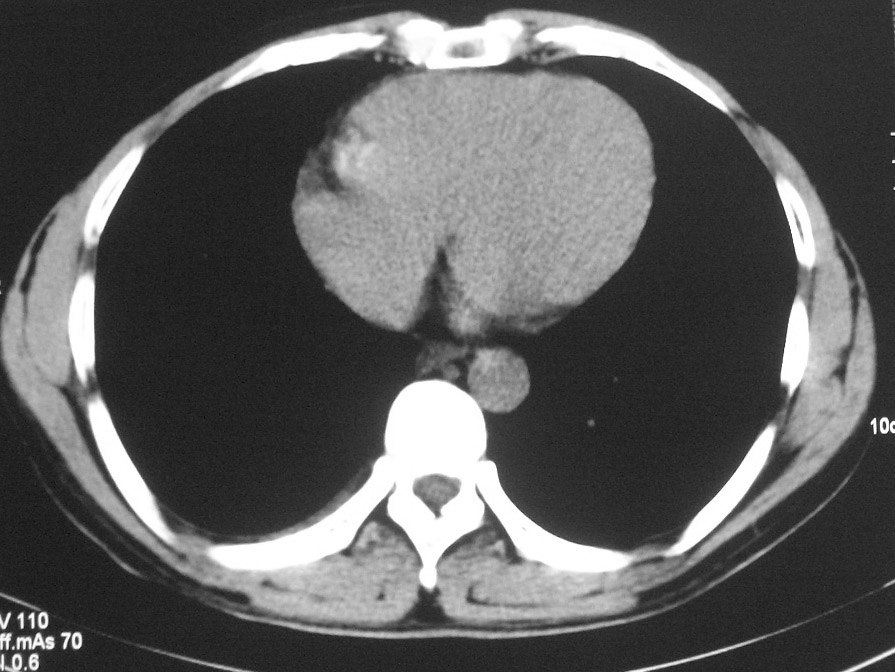

标题: CT5485:[原创]肺部占位请讨论

右上叶支气管肺癌并右上叶阻塞性不张,右侧少量胸腔积液.

右上肺中央性肺癌伴右侧胸腔少量积液!右上肺胸膜下还有一小病灶,不完全排除结核,但个人支持恶性肿瘤!建议早穿刺活检。

右肺上叶中央型肺癌并上叶肺不张、纵隔淋巴结肿大.右侧少量胸腔积液。

右上肺中心型肺癌并肺不张,纵膈淋巴结肿大。右侧少量胸腔积液。

右肺上叶不张,考虑中央型肺癌。右侧胸膜肥厚